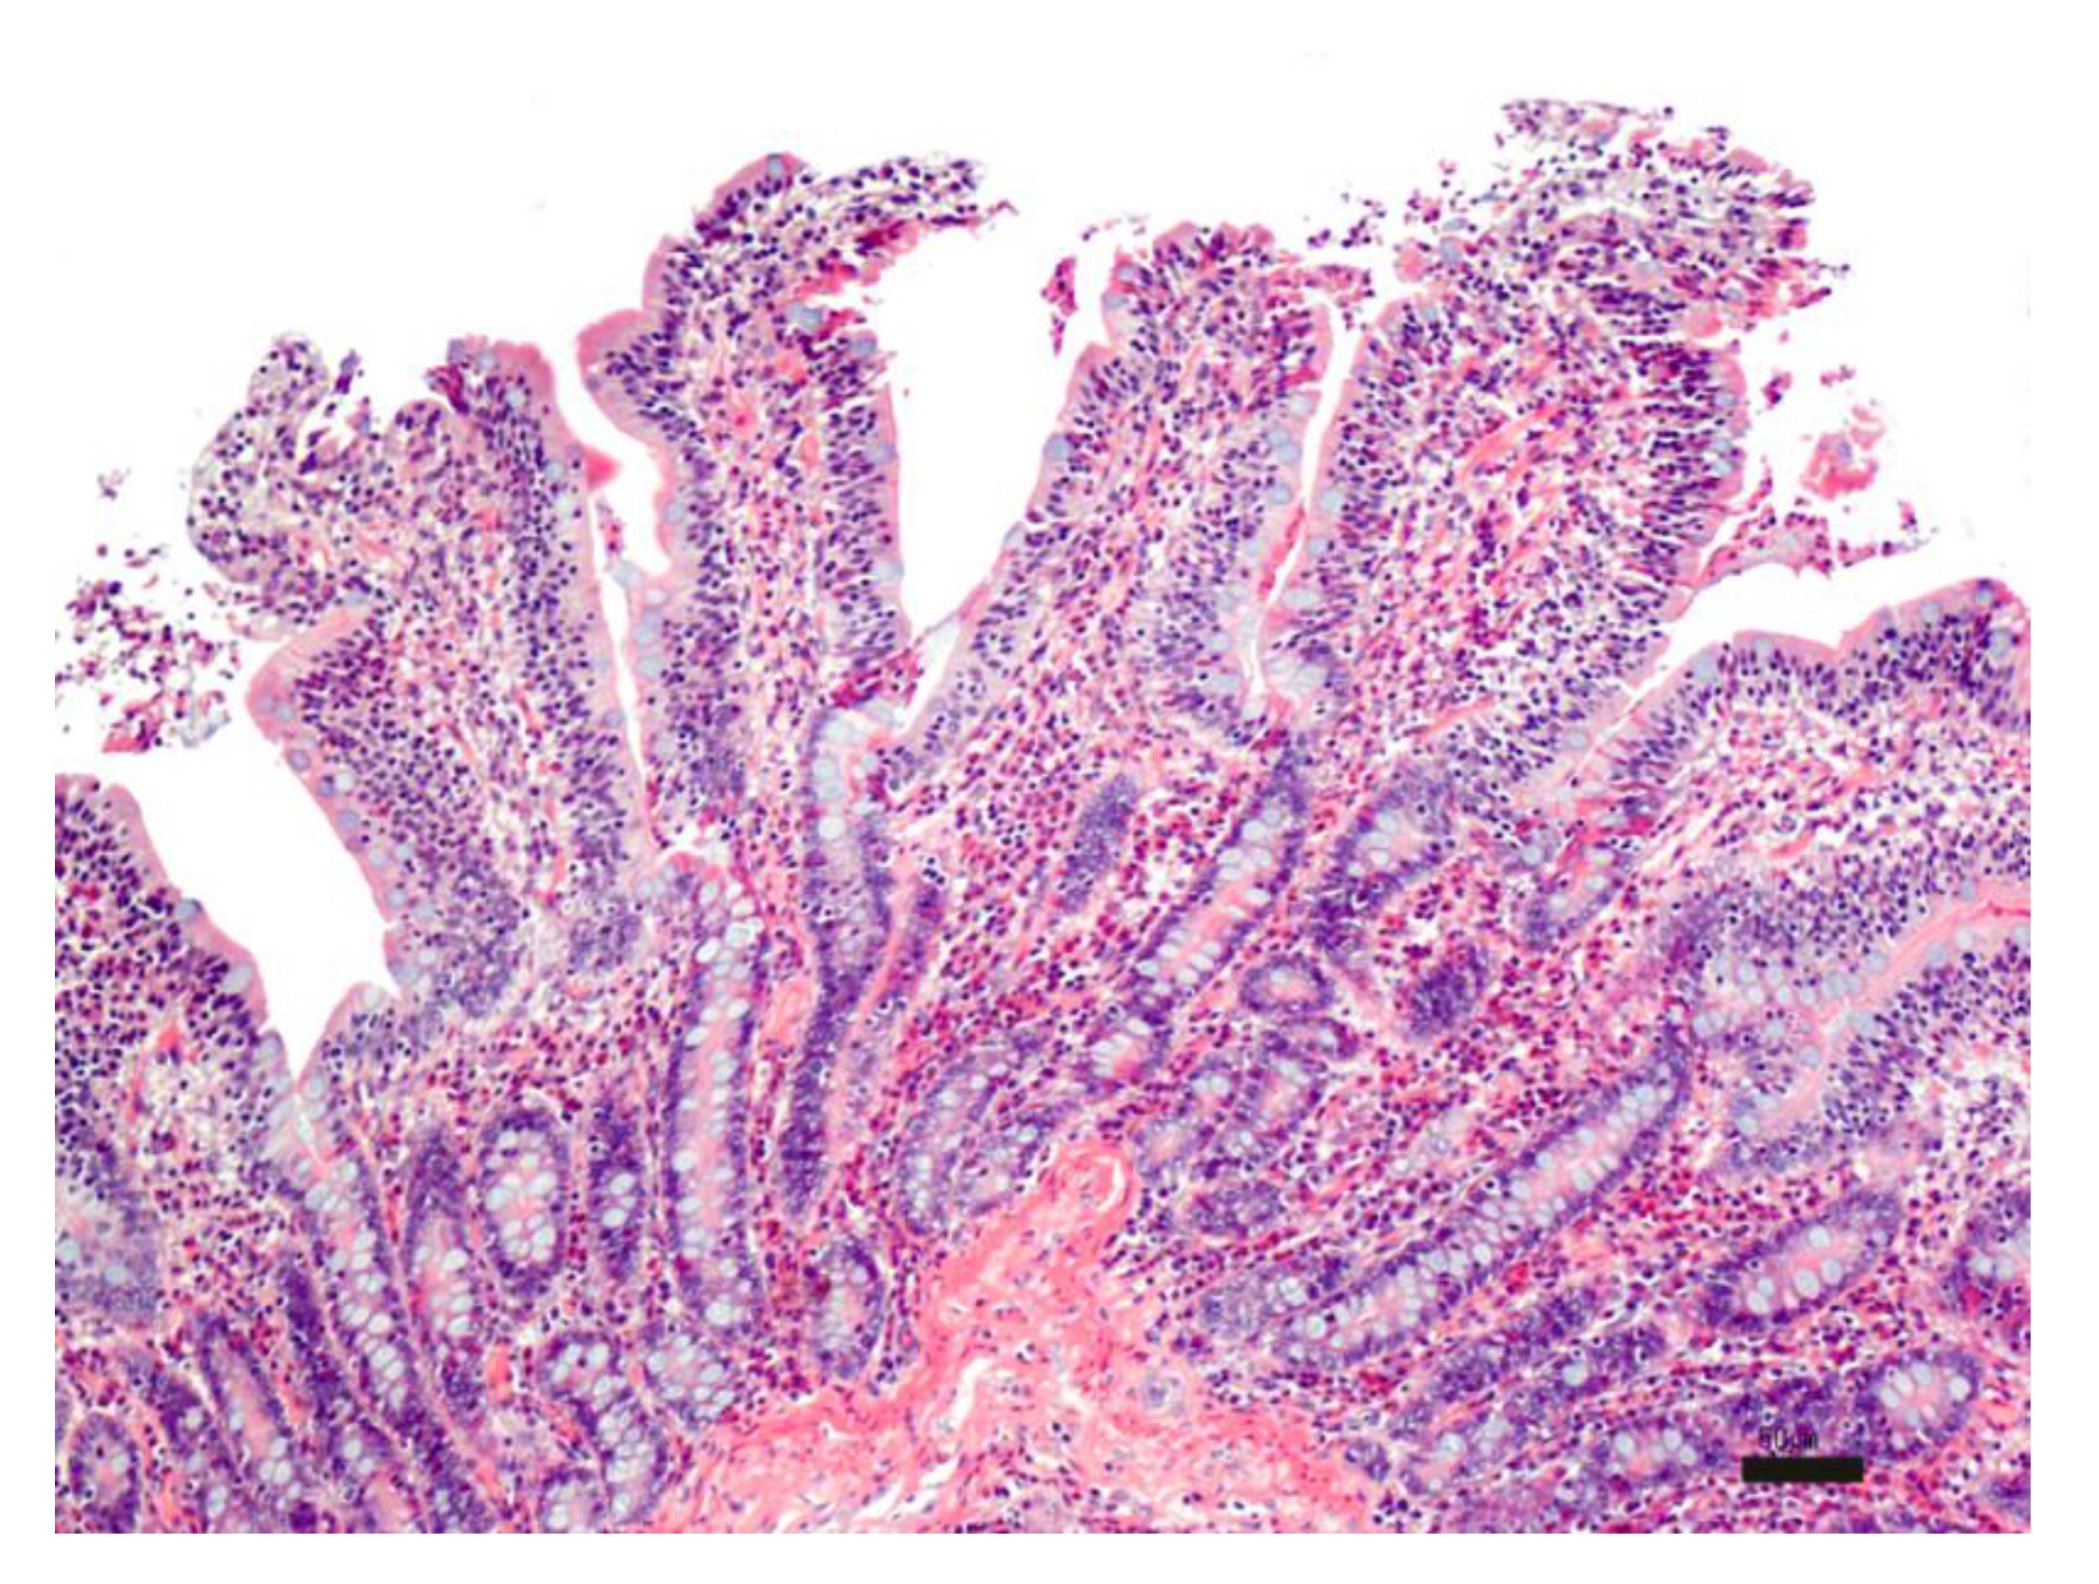

During the first part of the experiment, the morphology of the intestinal tissue exposed to different temperatures (25 °C and 37 °C), and experimental times (from 0 to 6 h) was evaluated. The time zero evaluation of the intestinal sections was characterized by a moderate inflammatory infiltrate expanding the lamina propria, composed mostly of lymphocytes and plasmacells and a lesser number of eosinophils and macrophages. Villi were blunted with apical fusion and lined by swollen epithelial cells with granular amphophilic cytoplasm and basal hyperchromatic nuclei. The moderate inflammatory infiltrate associated with villi blunting likely led to an alteration in the enterocyte absorption capacity and a probable reduction in SLN uptake (Figure 6).

Figure 6.

Histological evaluation of intestinal tissue at time zero: moderate, diffuse chronic lymphoplasmacellular and eosinophilic enteritis. HE; bar: 50 µm.